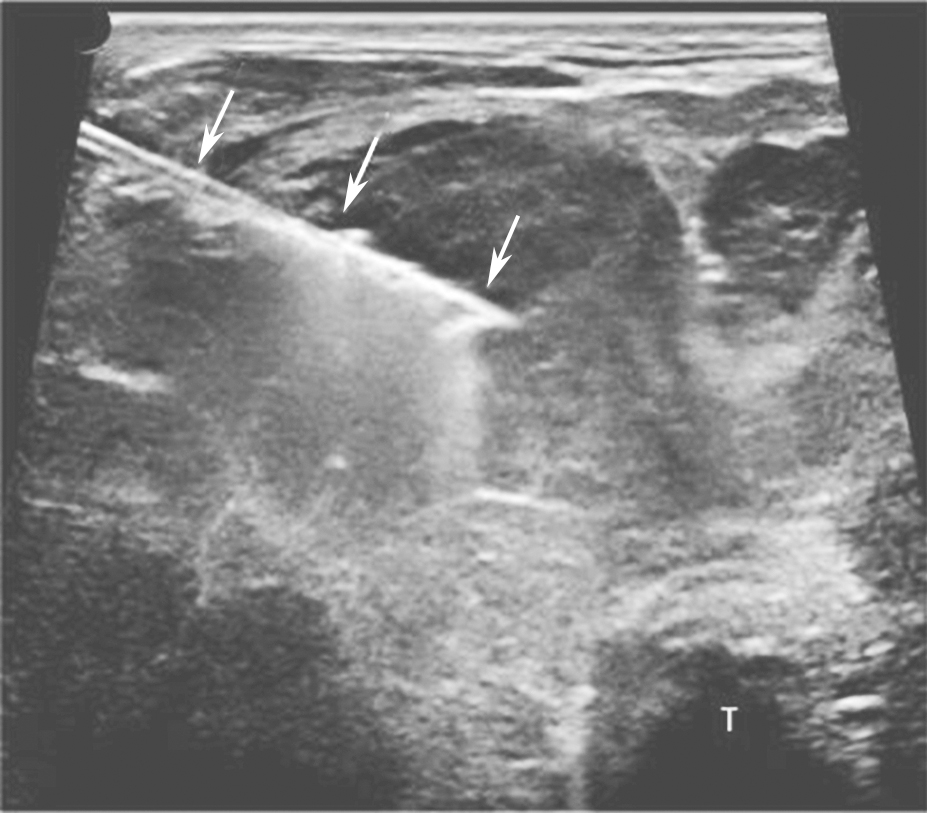

桥本甲状腺炎超声表现为甲状腺弥漫性增大,以前后径改变最为明显,峡部明显增厚。腺体包膜清晰完整,回声弥漫性不均减低(图2)。腺体内可见多个由淋巴组织、残余滤泡和上皮组织形成的无占位效应的低回声小结节。腺体广泛纤维化后体积可缩小。甲状腺下极附近淋巴结增大对于诊断有参考价值。

,T:气管.jpg)

图2颈部正中横切面:甲状腺腺体回声不均匀,峡部增厚,可见多个无占位效应的低回声小结节(箭头所示),T:气管